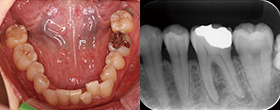

Case1 湾曲根管

• CC「左下奥違和感」主訴に来院

• 左下⑤6⑦Br除去→左下7 2次カリエス認める

• 湾曲大きく穿通せず…ハンドファイルで治療回数5回

EdgeSequel Sapphire™#15/.06テーパーにてグライドパス形成

• 作業長確認

最終拡大#40/.04テーパー